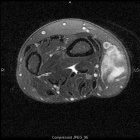

68 year old female with painless mass in right forearm

Zoom image: Radiological image Radiological image.